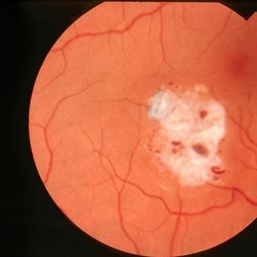

Tuberous Sclerosis

Oct 9 2012 by Alan D. Letson, MD

Small astrocytic hamartoma in asymptomatic 65-year-old woman with Tuberous sclerosis.

Photographer: Beverly Radcliffe

Condition/keywords: astrocytoma, hamartoma, tuberous sclerosis